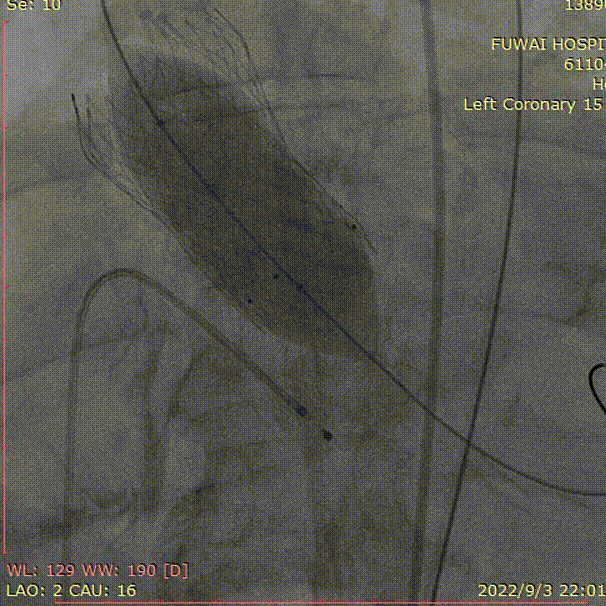

左冠造影

本例患者为72岁的老年男性,因外院诊断为急性心肌梗死而收入我院急诊,患者情况危急合并心源性休克,有急诊PCI指征,然而患者超声提示主动脉瓣中重度狭窄,经心外科和结构性心脏中心会诊后,考虑急诊TAVR,吴主任团队评估患者后,患者肾功能良好,先行急诊CT,然后直接快速上台行急诊TAVR,同时分析CT,为TAVR手术提供详细的参考,同时术中冠脉造影再次评估急诊PCI处理指征。患者病情危重,术前根据CT评估确定29型号VenusA-Plus瓣膜并且实现瓣膜预装。冠脉造影后吴永健主任当机立断,先行TAVR治疗,果然在球囊预扩张主动脉瓣时,出现循环崩快,立即心外按压,患者循环恢复,顺利植入瓣膜,然而钙化太重导致瓣架形态不佳,故大球囊后扩张,瓣架形态恢复。在麻醉科、超声科多学科协同下,吴永健主任团队顺利完成TAVR手术。患者术后即刻超声可见支架位置固定良好,瓣叶启闭运动正常,未见明显瓣周漏。患者心功能明显改善,恢复状态良好,手术圆满成功,患者术后恢复良好。